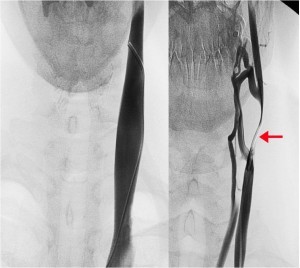

Chronic cerebrospinal venous insufficiency (CCSVI) is a newly described vascular entity. It is characterized by restricted venous outflow from the brain and spinal cord through the internal jugular (IJV) and/or azygos (AZ) veins (Figure 1), or sometimes, through the external vertebral plexuses. (1-5)

At 1 year follow up the EDSS was 3 again and the patient reported recurrent fatigue that she had been experiencing for several months. Further investigation revealed a CCSVI related left IJV tandem obstruction. At mid cervical level B-mode color Doppler demonstrated an IJV obstruction mirrored by an MRV imaging. In both cases a pencil tip pencil sign was demonstrated (Figure 2). The color Doppler assessment highlighted a left IJV dynamic flow obstacle caused by an extrinsic compression (Figure 2), that could be relieved by yawning.